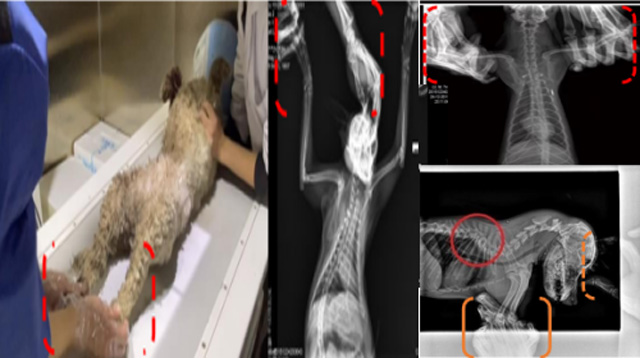

現(xiàn)在寵物醫(yī)療設(shè)備得到高速發(fā)展,現(xiàn)在有越來越多的寵物診療機(jī)構(gòu)配置X射線裝置如寵物DR。寵物骨折或者有其他疾病不能通過直觀看出來的。寵物診所醫(yī)生都會(huì)使用寵物DR來做輔助檢查。但是有時(shí)候?qū)櫸镝t(yī)生沒有加強(qiáng)防護(hù),就在寵物DR室給寵物拍X片做檢查。這樣也是會(huì)受到X射線的輻射。因?yàn)閄射線上崗是屬于職業(yè)病危害崗位。長(zhǎng)期的輻射會(huì)對(duì)人體造成一定的危害。寵物醫(yī)生也需要接受X射線照射的上崗前都必須進(jìn)行放射工作人員的職業(yè)健康體檢。體檢不合格的話是不能擔(dān)任放射工作的。未經(jīng)上崗前職業(yè)健康體檢的勞動(dòng)者從事接觸職業(yè)病危害作業(yè)的行為,已經(jīng)違反了《中華人民共和國(guó)職業(yè)病防治法》第三十五條規(guī)定,依據(jù)《中華人民共和國(guó)職業(yè)病防治法》第七十五條規(guī)定,需要進(jìn)行整改罰款。開展寵物放射診療活動(dòng),在日常工作中,對(duì)本機(jī)構(gòu)的X射線危害的職業(yè)病防治,需要知道并做到以下內(nèi)容: